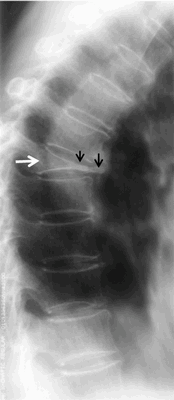

В некоторых случаях болезнь Кальве становится для травматолога-ортопеда или вертебролога случайной находкой, обнаруженной на рентгенограмме позвоночника. В диагностическом смысле рентгенография позвоночника наиболее информативна, если она проведена в боковой проекции. Для более детального изучения происходящих в позвонке изменений и с целью дифференциальной диагностики болезни Кальве пациента дополнительно обследуют при помощи МСКТ или КТ позвоночника.

В начале заболевания на снимках выявляется утолщение замыкательных пластинок и остеопороз центрального отдела тела измененного позвонка. Дальнейшее прогрессирование асептического некроза приводит к уменьшению высоты пораженного позвонка в среднем до ¼ его высоты в здоровом состоянии. При этом отмечается увеличение толщины межпозвоночных дисков, сверху и снизу примыкающих к неркотизирующемуся позвонку. Тело измененного позвонка больше сдавлено в переднем отделе, что выглядит на рентгенограмме как небольшая клиновидная деформация. Ширина его увеличена так, что тело позвонка выступает за пределы расположенных рядом с ним здоровых позвонков. Рентгенологически наблюдается зазубренность контуров тела уплощенного позвонка. Большая интенсивность изображения тела этого позвонка свидетельствует о развитии в нем некротических процессов.

Асептический некроз тел позвонков при болезни Кальве (рентгенография позвоночника)

Рентгенограмма грудного отдела позвоночника в боковой проекции. Остеохондропатия тела позвонка (болезнь Кальве): стрелкой указан пораженный позвонок.

Впервые заболевание описал Кальве в 1925 г. Кальве болезнь встречается очень редко, преимущественно у детей 4—12 лет. Остеохондропатия тела позвонка развивается в результате нарушения его кровоснабжения, причины которого не ясны. Поражается один позвонок в нижнегрудном или верхнепоясничном отделах позвоночника. Первым и основным симптомом является постепенно нарастающая боль в области пораженного позвонка. При пальпации позвоночника отмечается локальная болезненность, ограниченное напряжение мышц и небольшое выступание остистого отростка пораженного позвонка. Общая или местная температурная реакция и изменения в гемограмме отсутствуют. Рентгенологический симптомокомплекс — платибрахиспондилия, т. е. уплощение тела позвонка и его расширение. Высота тела позвонка снижается как в переднем, так и в заднем отделах, и он приобретает вид узкой полоски, выступающей кпереди на несколько миллиметров (рис.). Межпозвонковые диски в этом участке расширены.